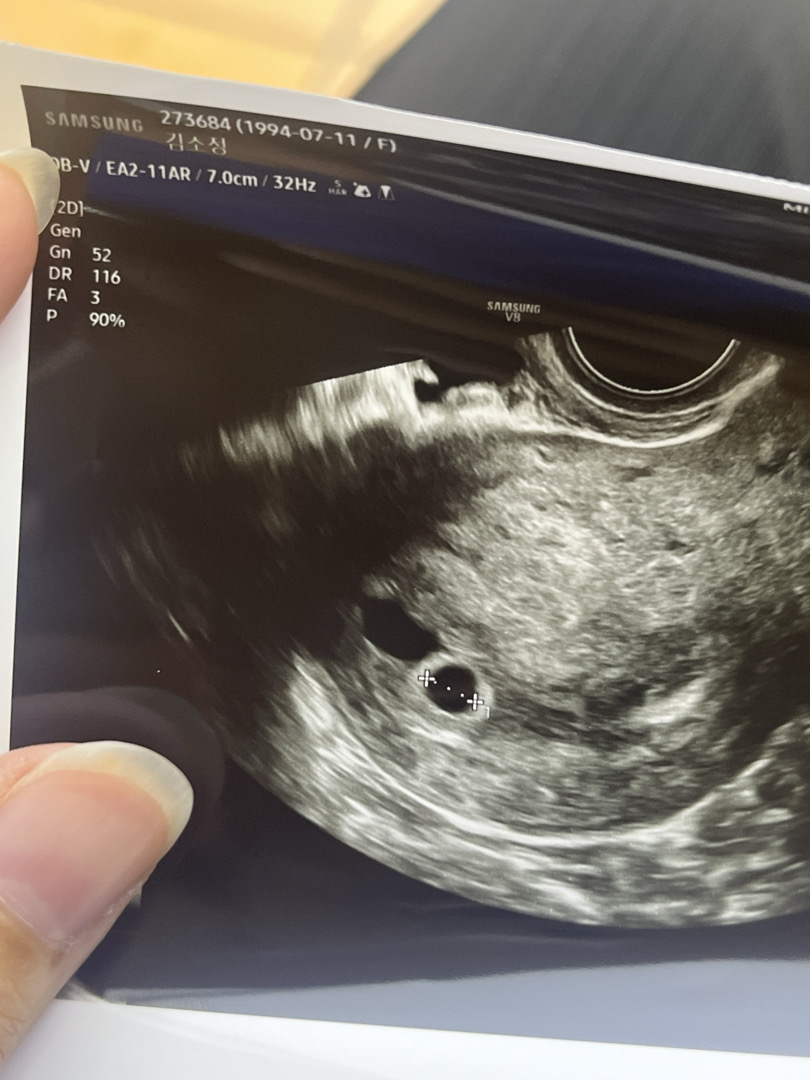

막생시작일 7월 31일 관계는 8월 21일 9월 6일 병원가니 피검사 189, 아기집 못봄 9월 17일 오늘 병원갔더니 아기집 진짜 작게 있고 난황은 못봤어요ㅜㅜ 아기집보다 피고임이 더 크게 있어서 질정 처방해주셨는데 첫임신이라서 너무 걱정되네요.. 다들 4-5주에 아기집 난황 보시던데 저는 6주6일인데 아기집도 너무작고 난황도 못보고 피고임까지 있다고하니 너무 걱정되고 우울해요ㅜㅜ